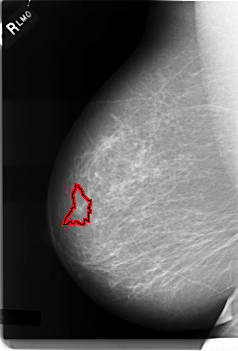

C_0003_1.RIGHT_MLO

FILE: C_0003_1.RIGHT_MLO.OVERLAY

TOTAL_ABNORMALITIES 1

ABNORMALITY 1

LESION_TYPE MASS SHAPE IRREGULAR MARGINS SPICULATED

ASSESSMENT 5

SUBTLETY 4

PATHOLOGY MALIGNANT

TOTAL_OUTLINES 1

BOUNDARY